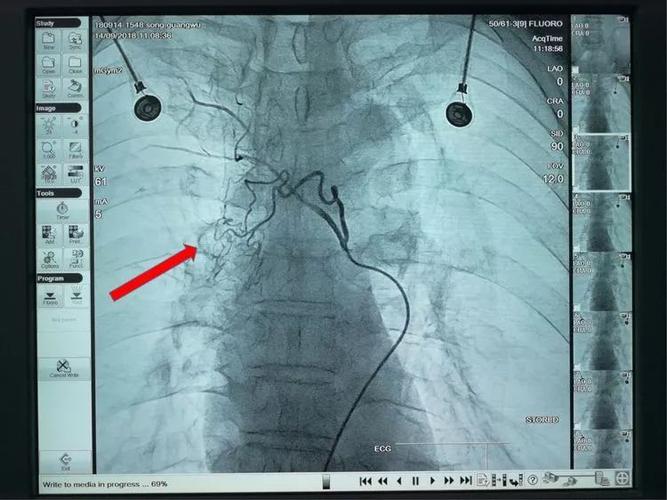

第504期肺癌患者经过三次支气管动脉化疗栓塞后肿瘤几近消失建华医院